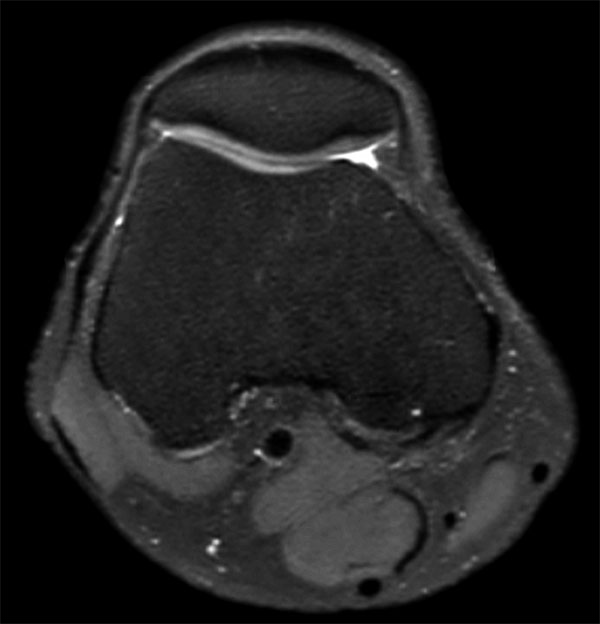

Comprehensive 3D knee imaging with MSK VIEW